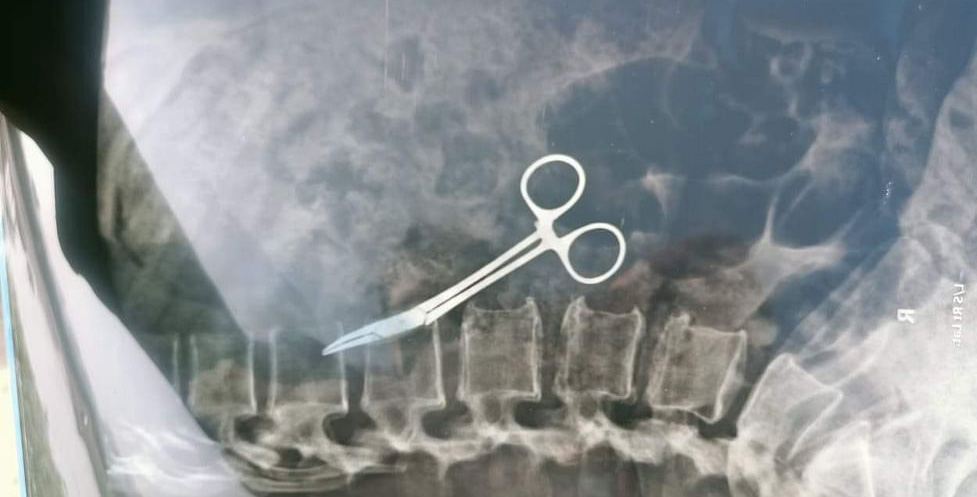

او توضیح داد: اخیراً وقتی او به ما مراجعه کرد، درخواست عکسبرداری با اشعه ایکس کردیم که در نهایت وجود قیچی داخل شکم او مشخص شد.

یک زن در بنگلادش که در سال ۲۰۰۲ عمل برداشتن کیسه صفرا را انجام داده بود، دائما از درد شکم رنج میبرد تا اینکه پس از ۲۰ سال مشخص شد یک قیچی جراحی در شکمش جا مانده است.

جراحان در بنگلادش یک قیچی را که ۲۰ سال پیش در داخل شکم یک زن باقی مانده بود، طی یک عمل جراحی برداشتند.